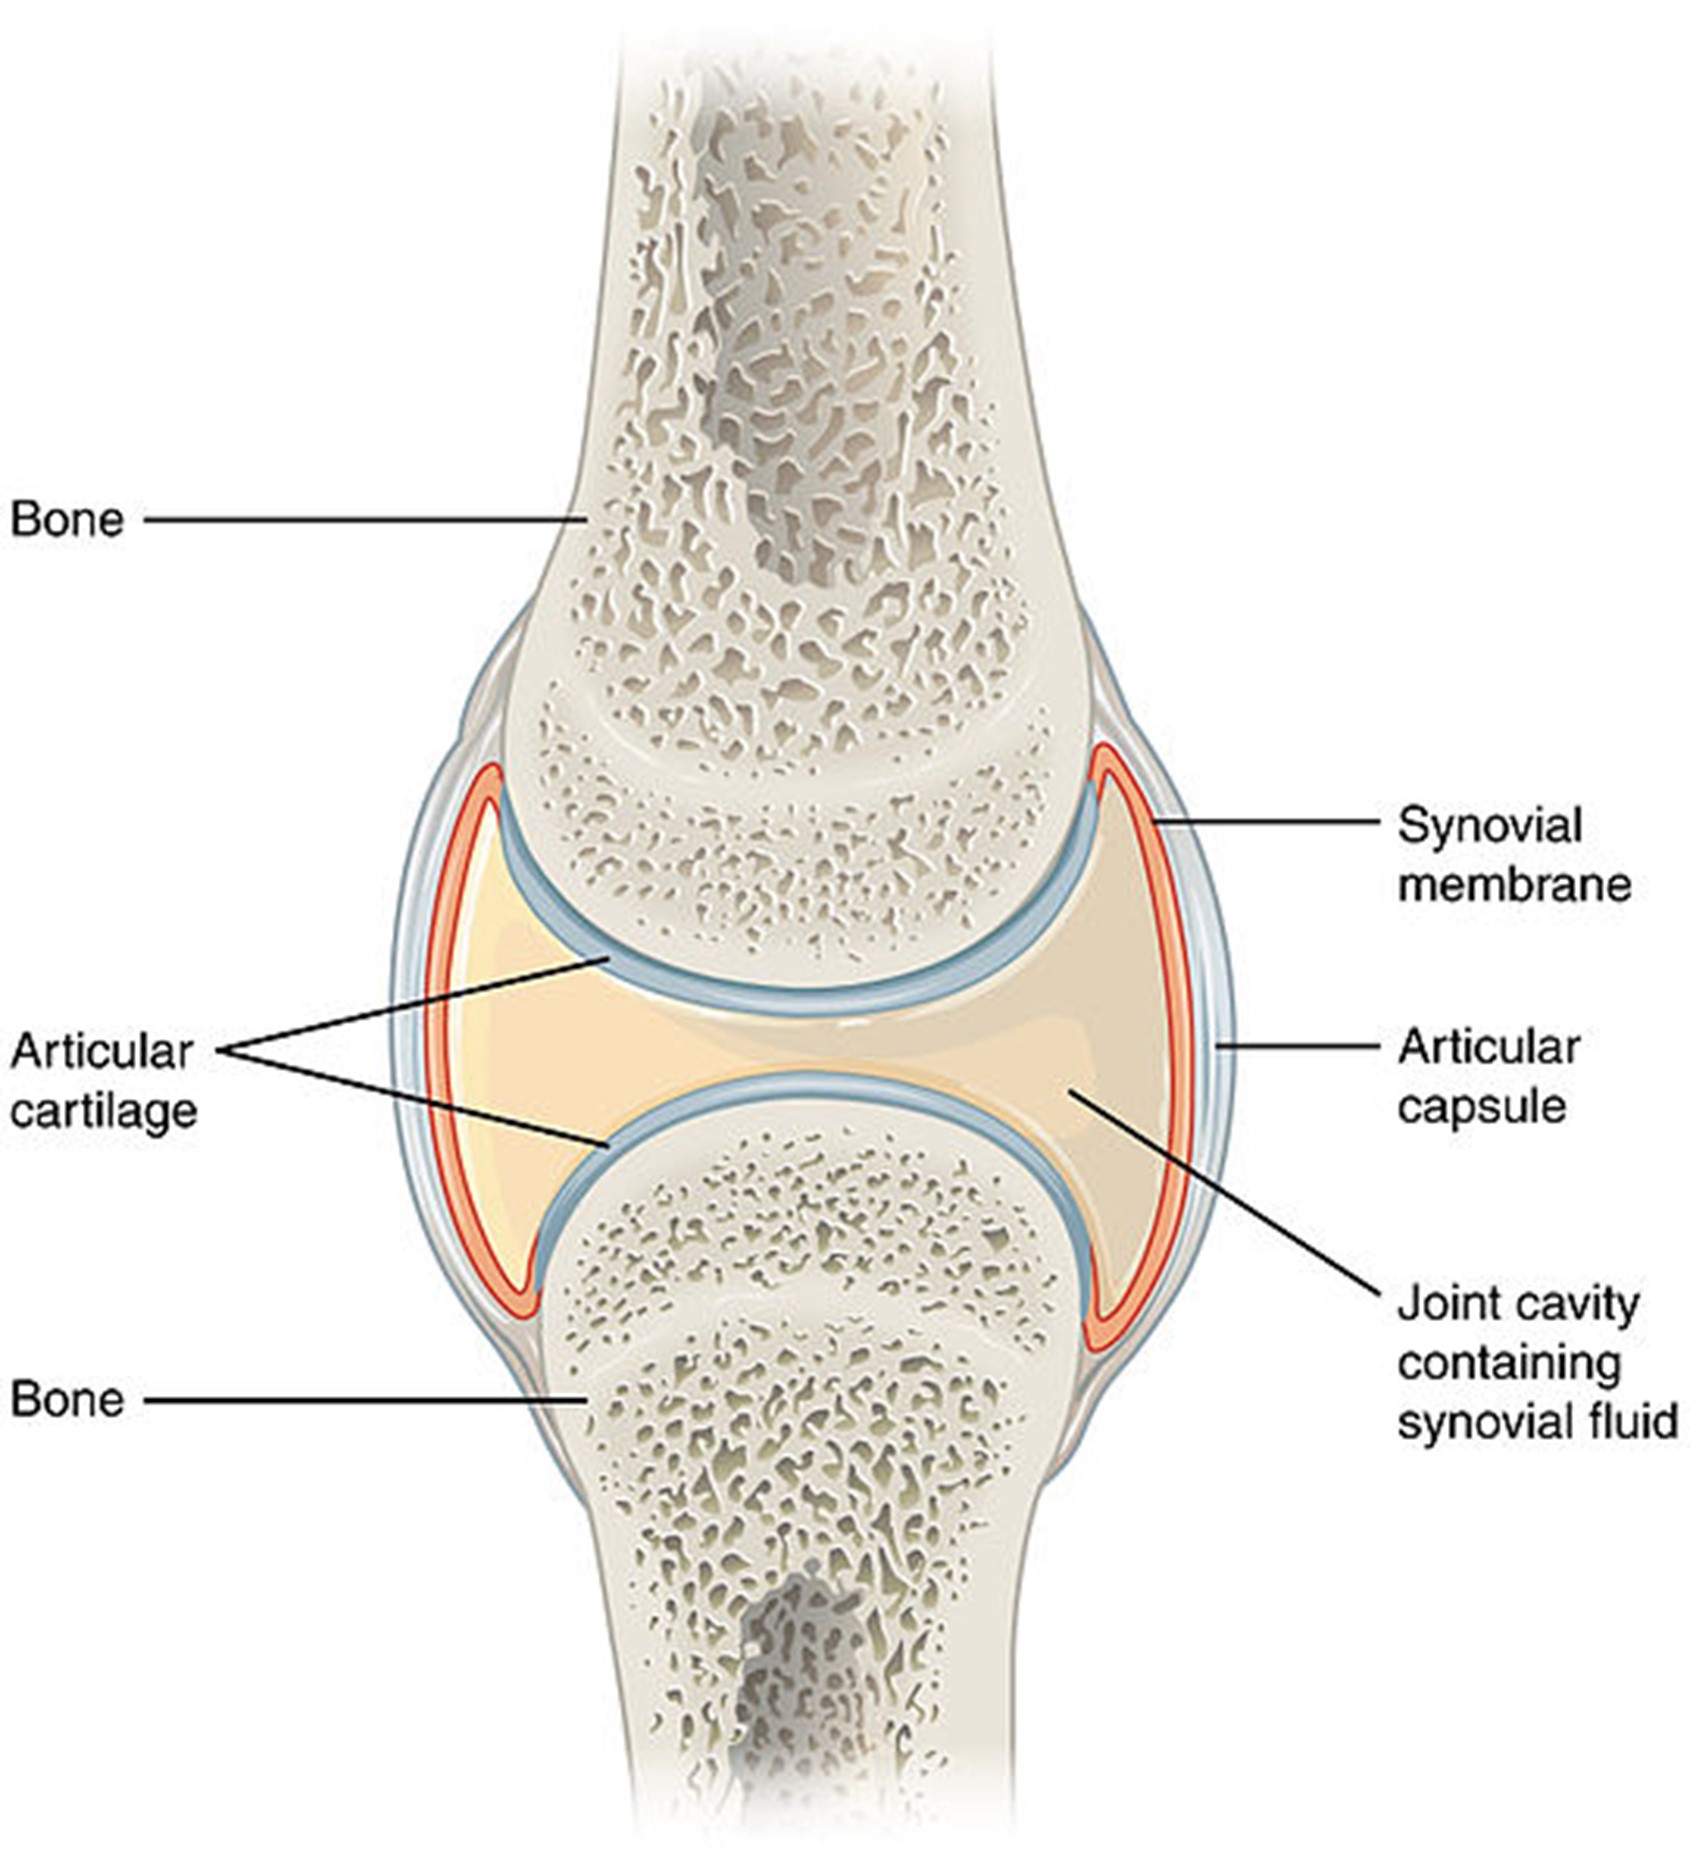

Anatomy and Physiology

Figure 2

Close-Up of Joint

(Open Stax College, 2013a)